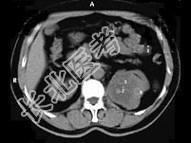

- 多项选择题男,65岁, 左侧腰背部胀痛伴无痛性全程血尿3个月余,CT平扫及增强检查如图所示, 下列说法正确的是 ( )

A、平扫时见左肾上极有一软组织肿块影,其边界较清楚

B、增强扫描肾皮质期可见肿块明显强化,其内亦有无强化区

C、增强扫描肾实质期可见肿块强化迅速下降,但密度比平扫时仍要高

D、考虑为左侧肾癌

E、考虑为左侧肾错构瘤